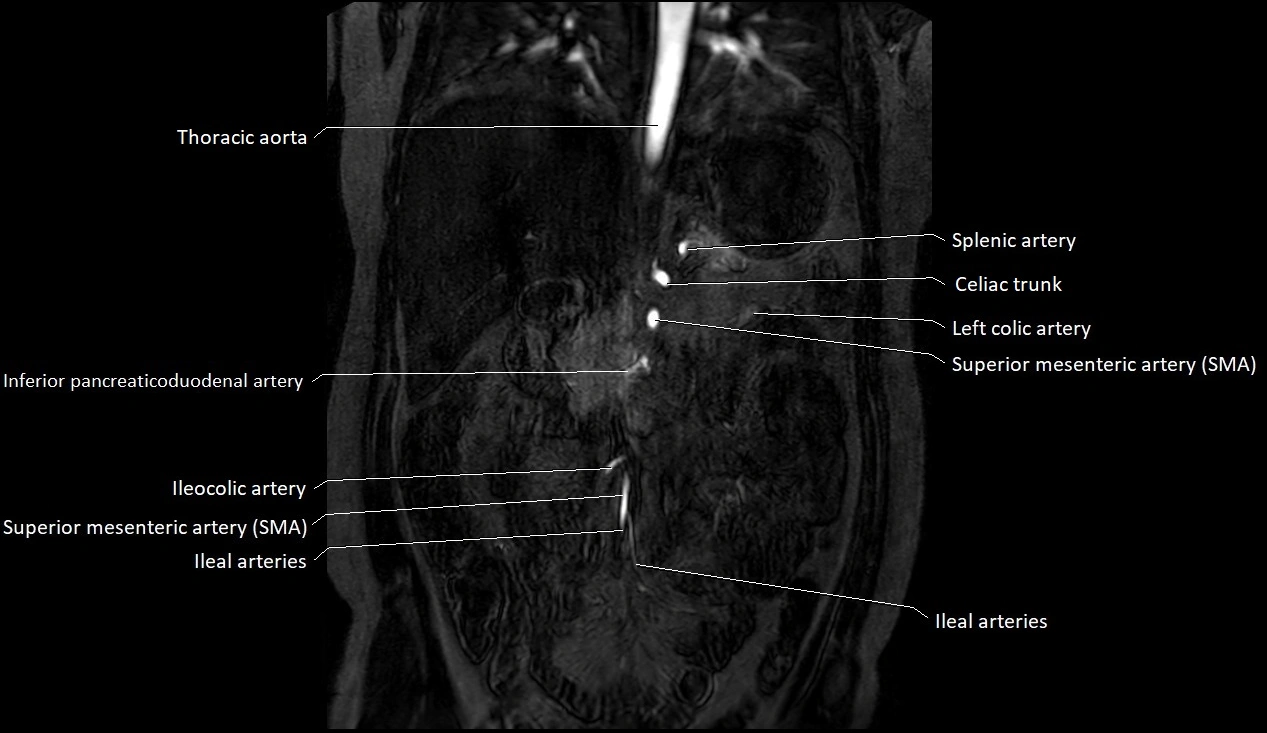

CT images

image